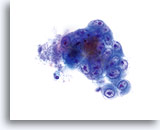

Kernen zijn vergroot, nemen vaak meer dan 2/3 van het cytoplasma in beslag en blijven doorgaans rond tot ovaal, met golvende celkernmembranen.

60x